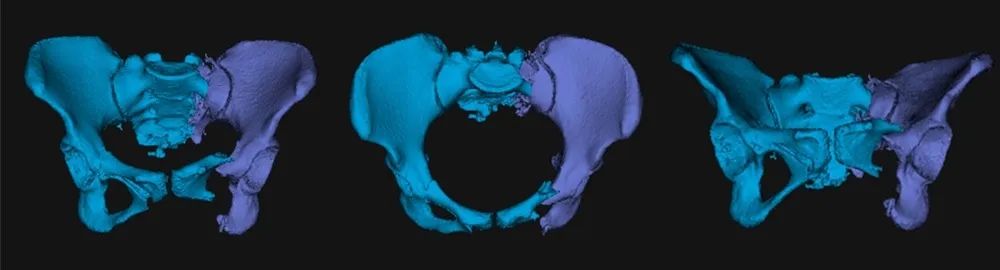

图二:患者术前影像资料

该患者为年轻女性,伤势严重且伤后等待救治时间较长(伤后13天接受手术),除了骨盆骨折之外,还合并胸腰椎多发骨折并不全瘫,肾、脾挫伤。若采用传统术式,损伤较大,且需要分期治疗骨盆骨折及腰椎骨折,同时还有继发脏器出血的风险。副院长孙涛、东院创伤一科主任洪焕玉及其团队反复讨论后决定实施创新术式,采用目前全球最先进的“智能化骨科手术机器人全流程辅助骨盆骨折闭合复位内固定手术”治疗方式。

术前,手术团队进行了周密的准备,基于患者术前影像,借助基于AI与大数据的自动手术规划,将患者健侧肢体进行镜像配准,通过精细化自动分割与重建,实现个性化、定量化的复位规划。

图三:自动分割与重建

图四:人工智能复位规划